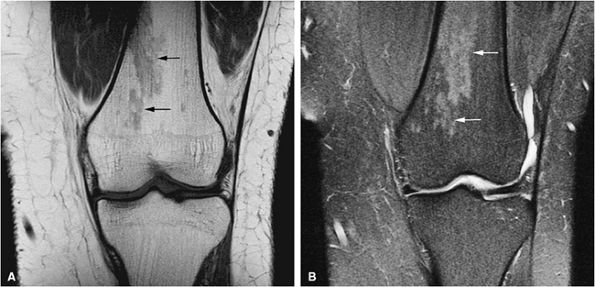

FIGURE 13.73 ● Accumulation of lipid in reticuloendothelial cells in Gaucher disease. Patchy low-signal-intensity marrow infiltration (arrows) can be seen on a coronal T1-weighted image of the pelvis and proximal femurs (A) and on a coronal T1-weighted image of the knees (B). There may be relative sparing of the epiphyses and apophyses until later stages of disease.

|